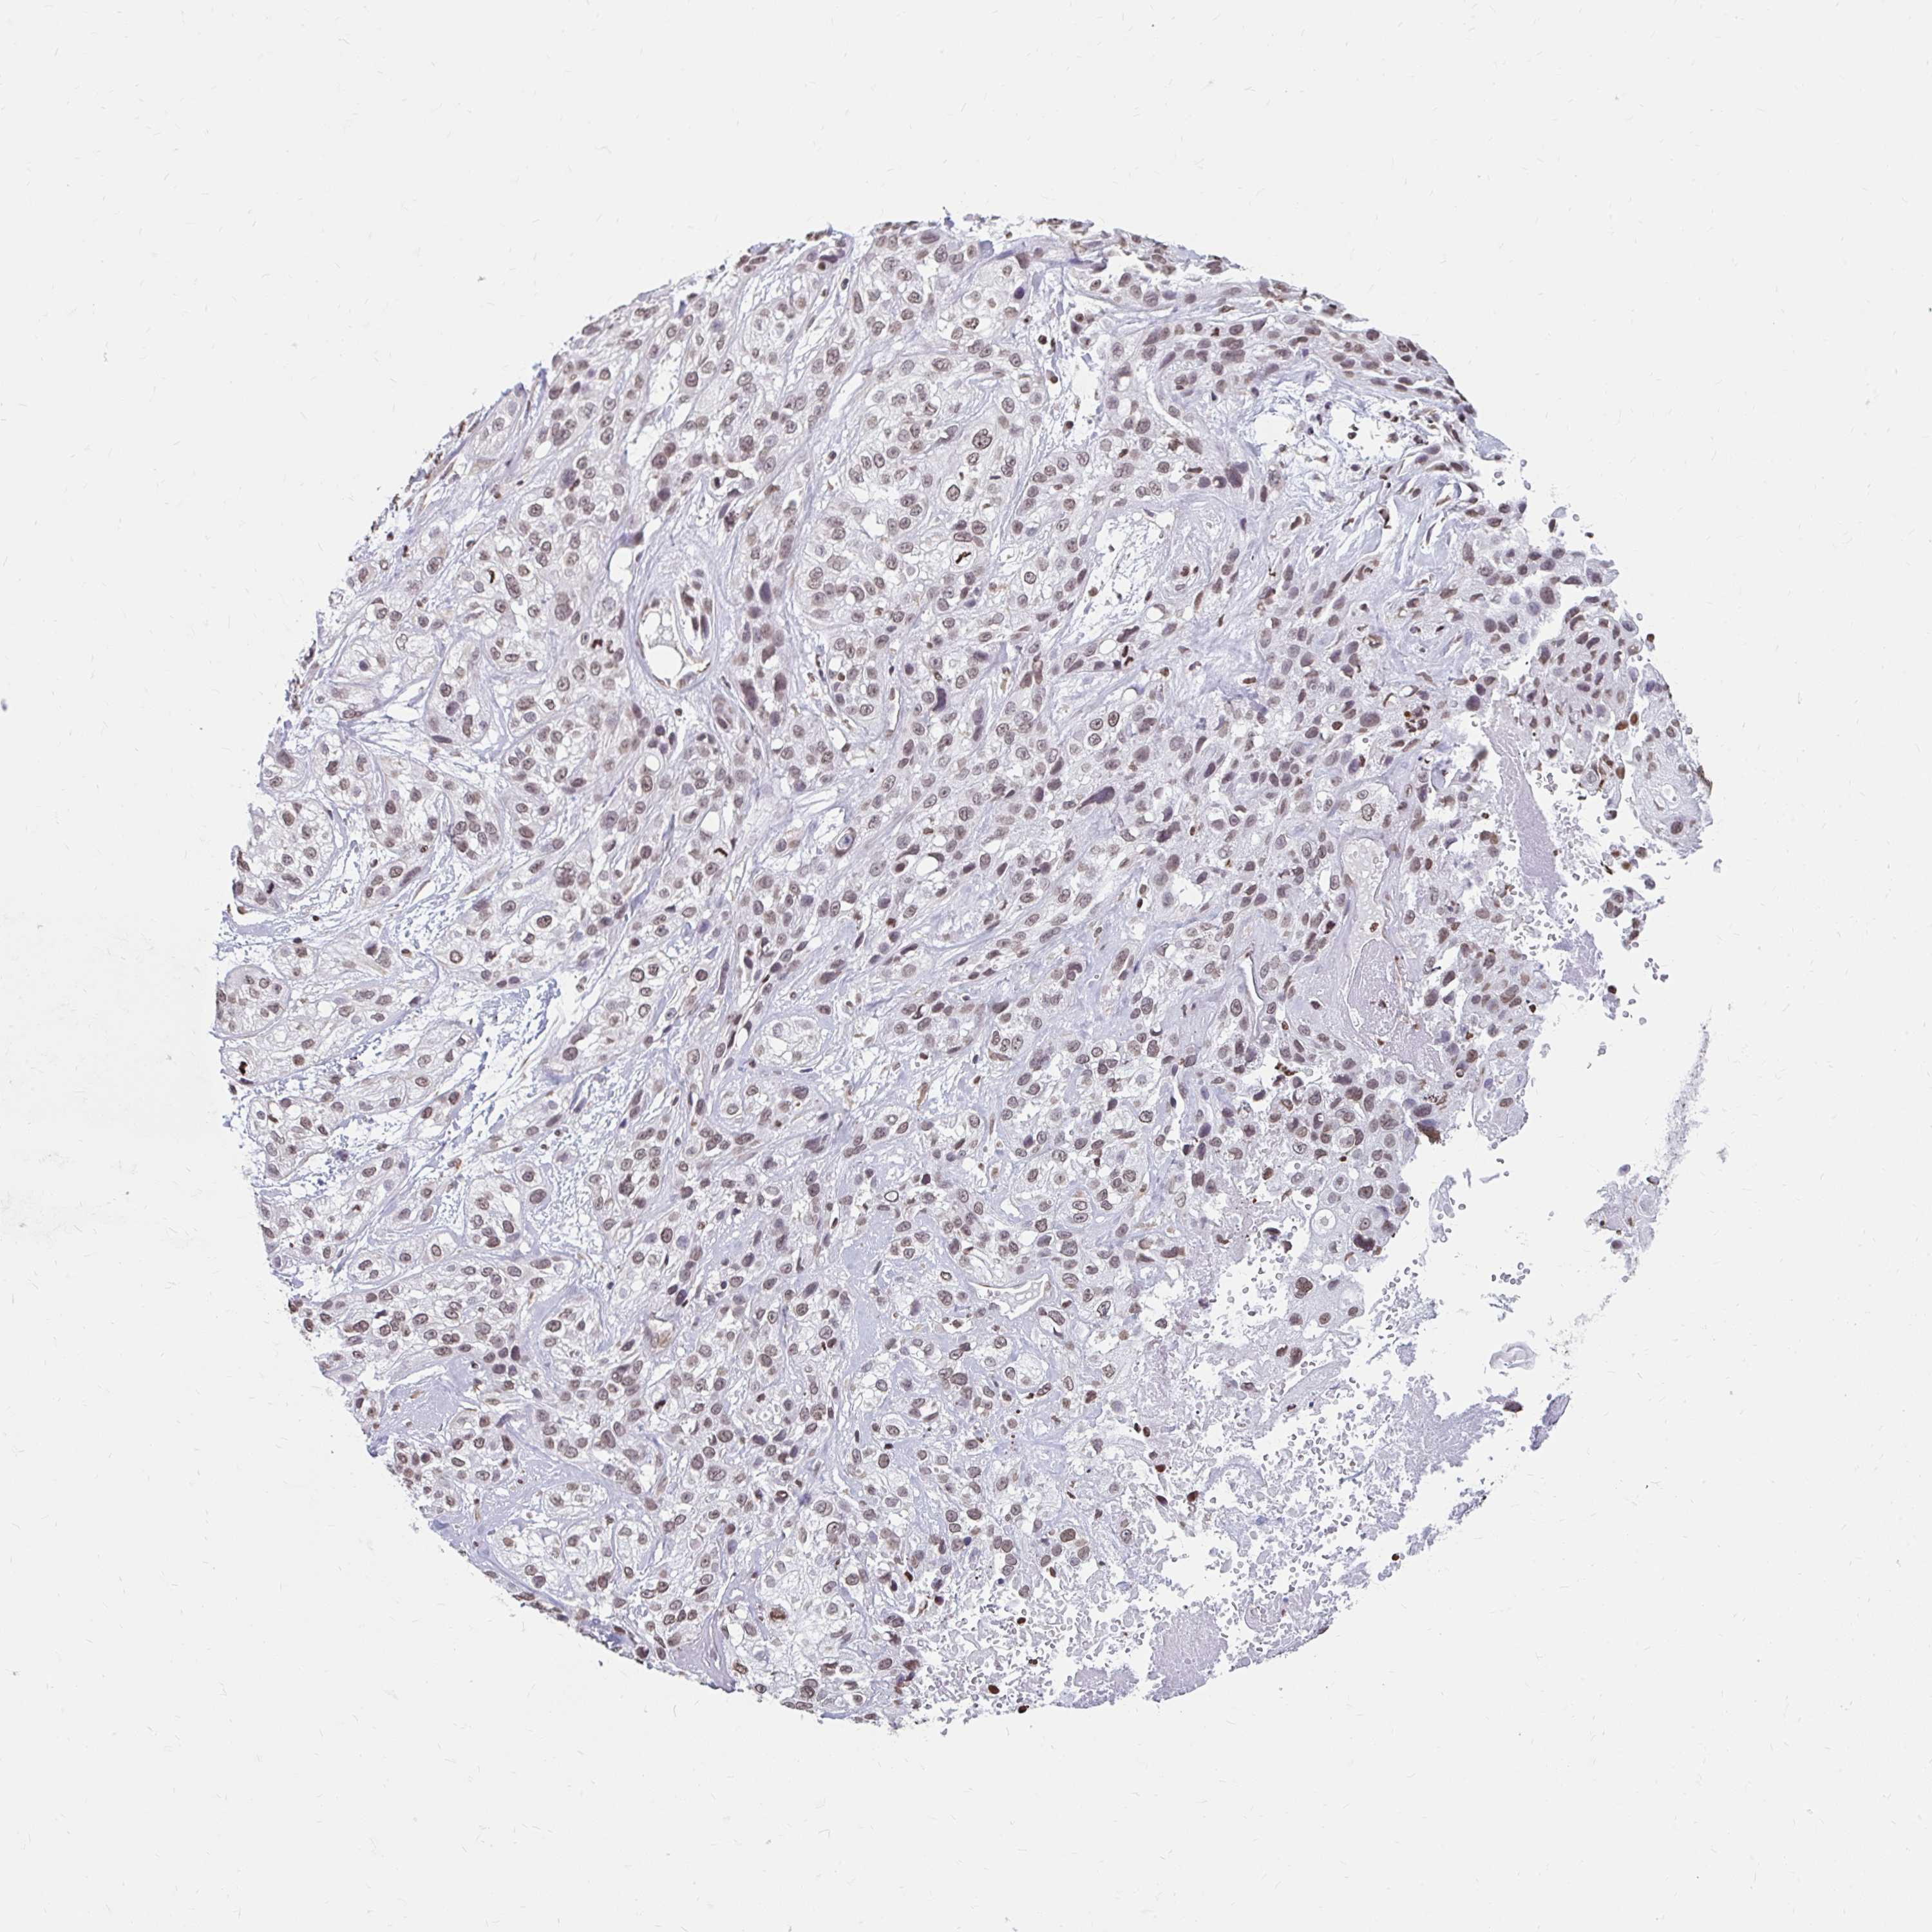

SKIN CANCER - Protein expressioni

A mouse-over function shows sample information and annotation data. Click on an image to view it in a full screen mode. Samples can be filtered based on level of antibody staining by selecting one or several of the following categories: high, medium, low and not detected. The assay and annotation is described here.

Antibody stainingi

Antibody staining in the annotated cell types in the current human tissue is reported as not detected, low, medium, or high, based on conventional immunohistochemistry profiling in selected tissues. This score is based on the combination of the staining intensity and fraction of stained cells.

Each image is clickable and will lead to virtual microscopy that enables deeper exploration of all samples and also displays staining intensity scores, fraction scores and subcellular localization as well as patient and tissue information for each sample.

Antibody HPA053748

Staining

High

Medium

Low

Not detected

Intensity

Strong

Moderate

Weak

Negative

Quantity

>75%

75%-25%

<25%

None

Location

Nuclear

Cytoplasmic/membranous

Cytoplasmic/membranous,nuclear

Basal cell carcinoma

Squamous cell carcinoma, NOS